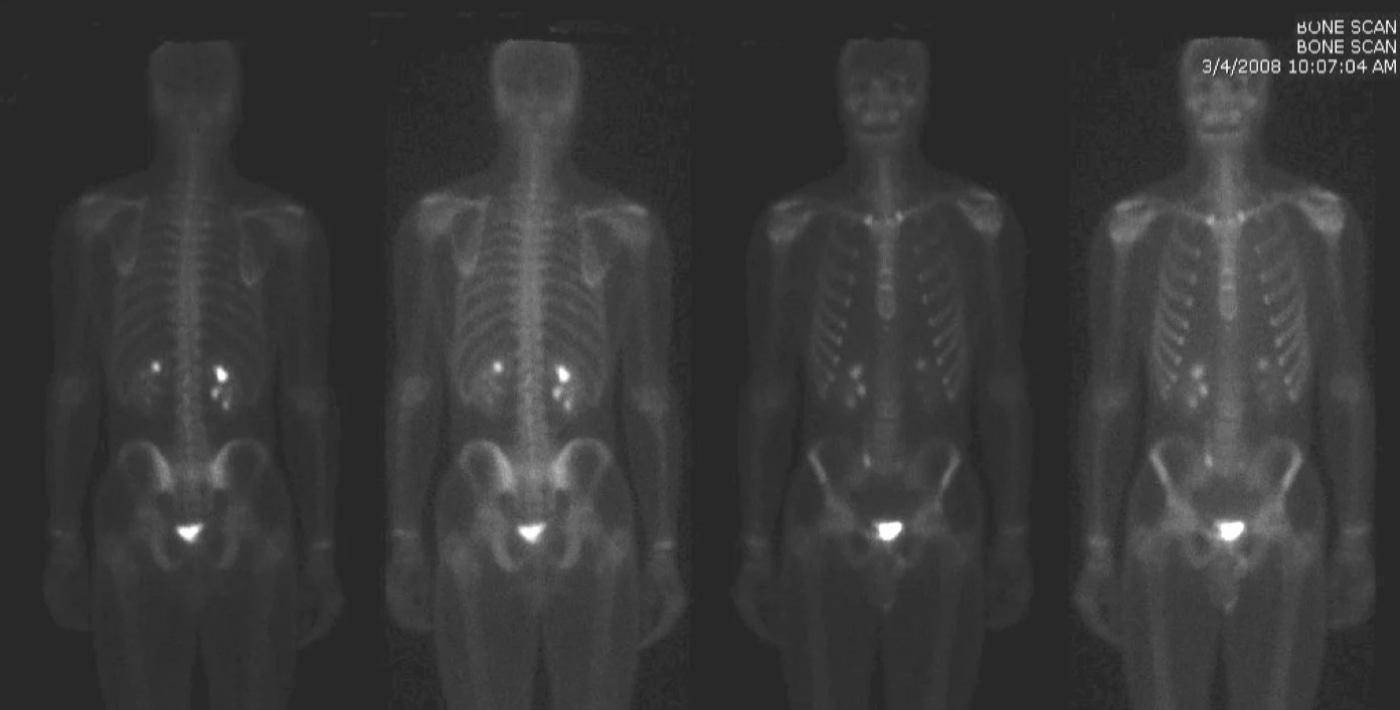

PET scan image of a cancer patient showing cancerous lymph nodes

As I write this, I am approaching my third of six rounds of chemotherapy. I have lymphoma, which if left untreated would be fatal. Sobering news, but I have a good prognosis. I am optimistic about the cure. I’m also taking my illness as an opportunity for reflection.